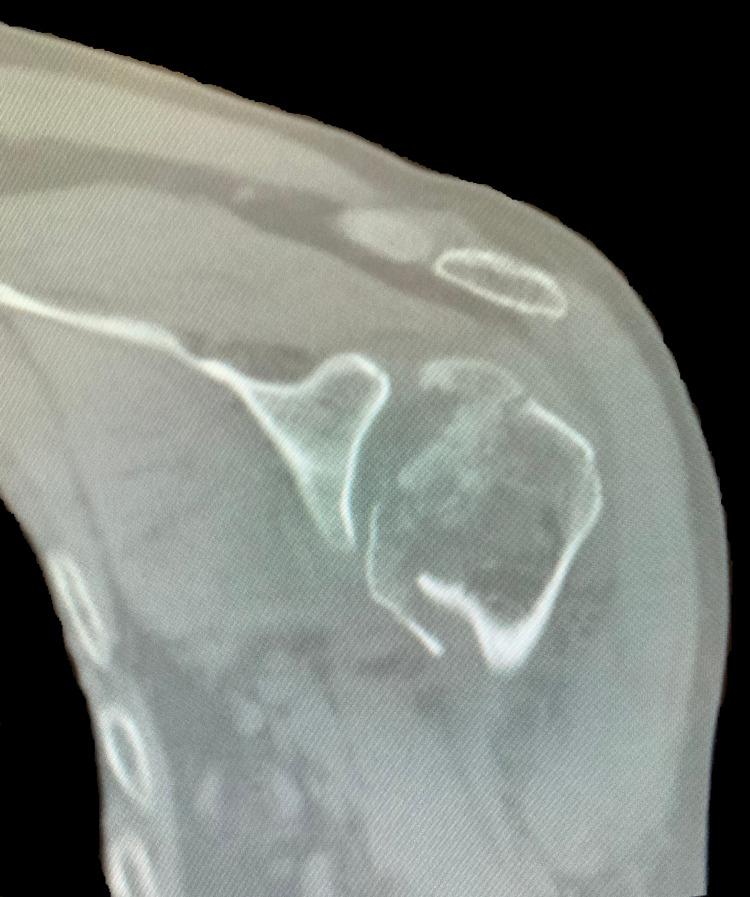

This report presents a previously undescribed case and treatment of bilateral four-part proximal humerus (PH) fracture-dislocations presented in a 61-year-old Caucasian male patient following a first-time seizure episode. The patient was treated with bilateral reverse total shoulder arthroplasty due to pre-existing glenohumeral arthritis and rotator cuff atrophy. The surgery was successful, and the patient's postoperative recovery was uneventful. Fractures of the proximal humerus are a relatively common adult osteoporotic fracture; however, posterior fracture-dislocations of the PH, frequently related to motor vehicle accidents, seizures, or electrical shock, are remarkably scarce. A treatment algorithm for these injuries is lacking.

本报告介绍了一例此前未被描述的双侧四部分近端肱骨(PH)骨折脱位病例及治疗情况,该病例发生在一名61岁的白种男性患者首次癫痫发作之后。由于患者术前存在盂肱关节炎和肩袖萎缩,故对其进行了双侧反式全肩关节置换术。手术成功,患者术后恢复顺利。近端肱骨骨折是一种相对常见的成人骨质疏松性骨折;然而,PH的后脱位骨折,常与机动车事故、癫痫发作或电击有关,却极为罕见。目前尚缺乏针对这些损伤的治疗方案。